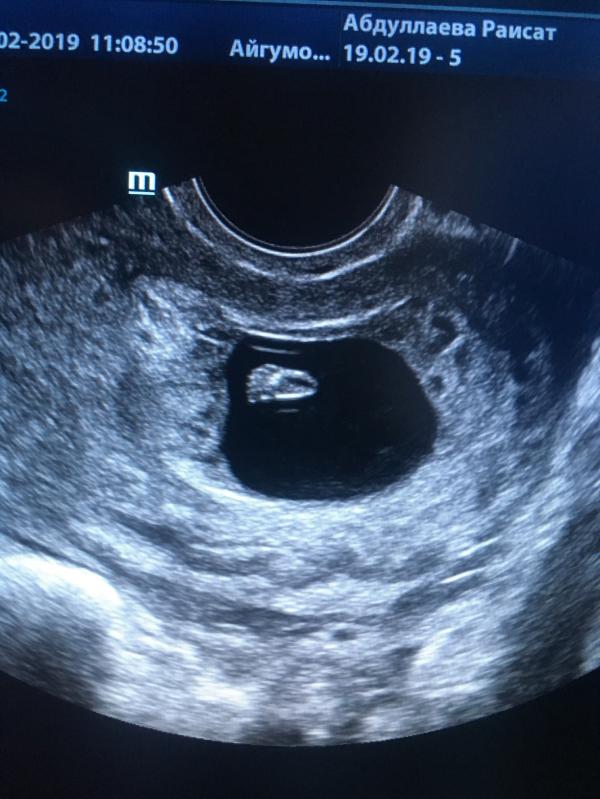

Наше первое узи😍😍😍😍

Мне сказали что похожа на девочку 🙈Хотелось бы узнать ошибались ли с полом кому нибудь в 12 недель и 3 дня))?